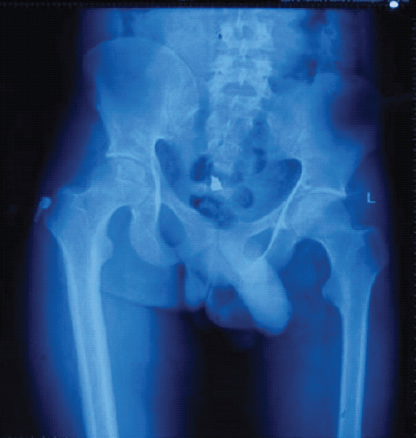

X-rays revealed thin femur and tibial diameters on the affected side compared to the contralateral limb (Fig. 1).

Figure 1: X-ray of bilateral hip with pelvis with femur to compare femoral width between poliotic (L) and non-poliotic limb (R).